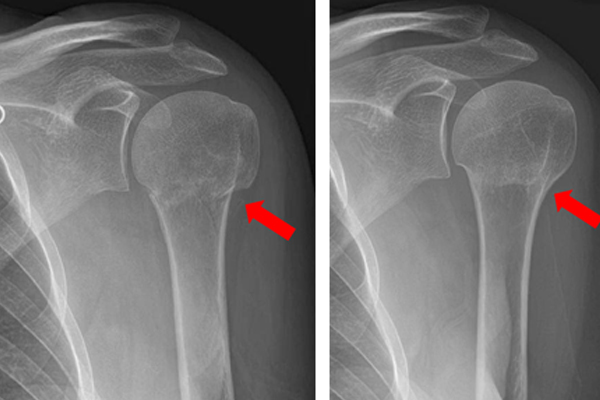

ROTATOR CUFF TEARS